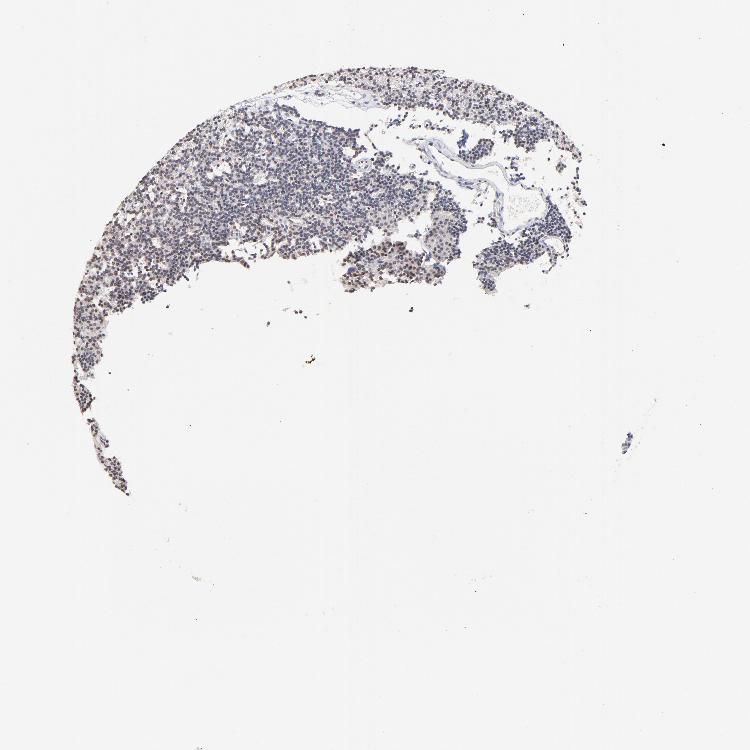

PARATHYROID GLAND - Antibody stainingi

Antibody staining in the annotated cell types in the current human tissue is reported as not detected, low, medium, or high, based on conventional immunohistochemistry profiling in selected tissues. This score is based on the combination of the staining intensity and fraction of stained cells.

Each image is clickable and will lead to virtual microscopy that enables deeper exploration of all samples and also displays staining intensity scores, fraction scores and subcellular localization as well as patient and tissue information for each sample.

Antibody HPA003030

Glandular cells Not detected